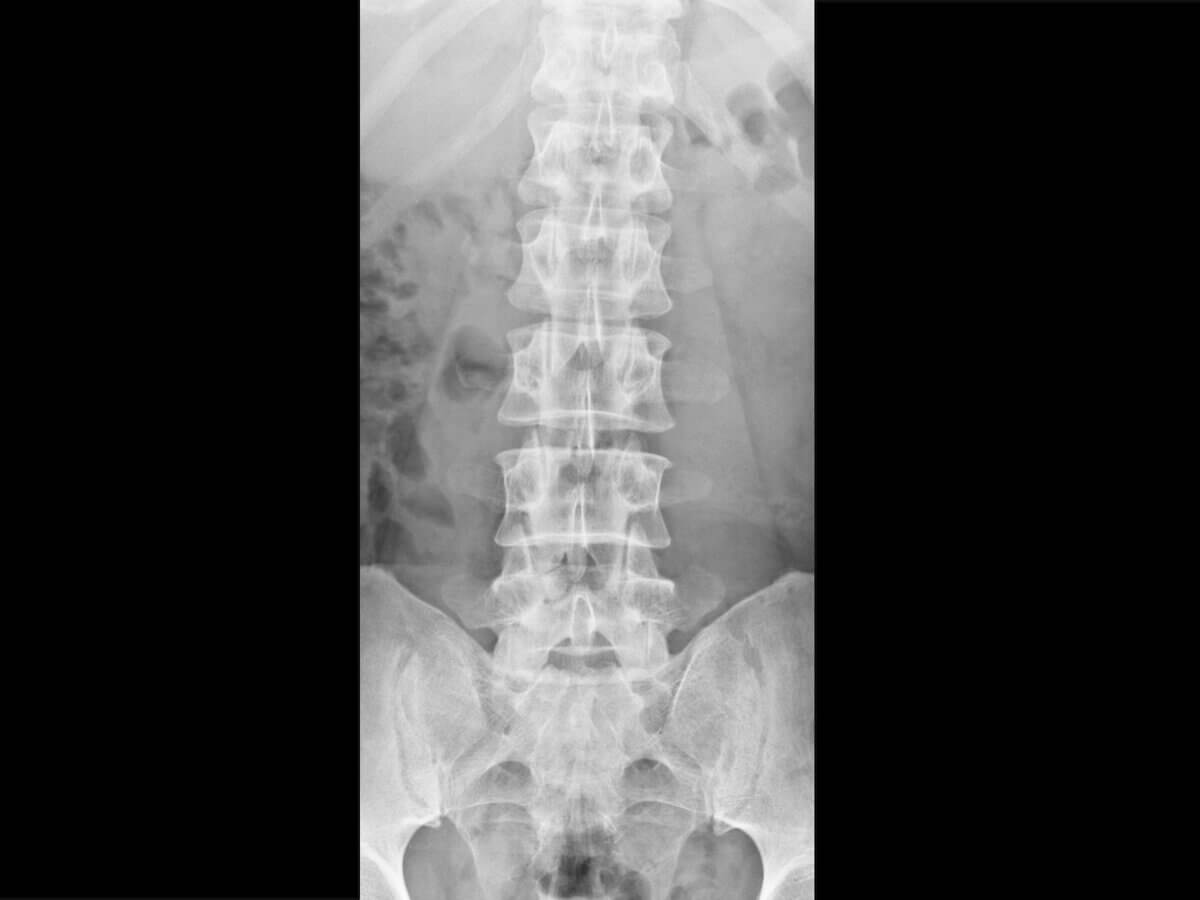

Röntgen-LWS

Synonyme: Röntgenaufnahme der LWS, Röntgen der Lendenwirbelsäule

Englisch: lumbar spine x-ray

Als Röntgen-LWS bezeichnet man die konventionelle Röntgenuntersuchung der Lendenwirbelsäule. Sie dient der Beurteilung von Wirbelkörpern, Bandscheibenfächern, Wirbelgelenken und Achsverhältnissen.

Beurteilt werden u.a.:

- Form und Höhe der Wirbelkörper

- Weite der Bandscheibenräume

- Alignment bzw. Achsstellung

- Vorhandensein von Osteophyten oder Sklerosierungen

- Frakturlinien oder Sinterungen

Zusätzlich werden die Weichteilschatten auf Auffälligkeiten überprüft.